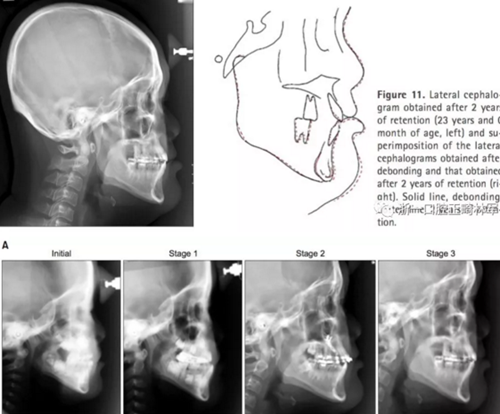

頭側結果顯示上頜輕度后縮(SNA 79.1°; A to N,-5.0mm;A到VRP水平距離為57.5mm),下頜輕度前突(SNB,80.2°,Pog-N-7.2mm;POG到VRP水平距離,57.4mm),低角ANB(-1.1°),正常下頜平面角(FMA,29.5°),正常下頜角(119.8°),上頜切牙斜度正常(U2 to SN,106.7°)和下頜切牙的舌傾角(IMPA,85.0°)。正常的覆合和覆蓋(覆合,1.7mm,覆蓋,1.9mm)(圖8和9,表3)。

2年后隨訪提示治療結果得到保持(圖10,11,表1-3),不同階段的頭側重疊結果見圖12。